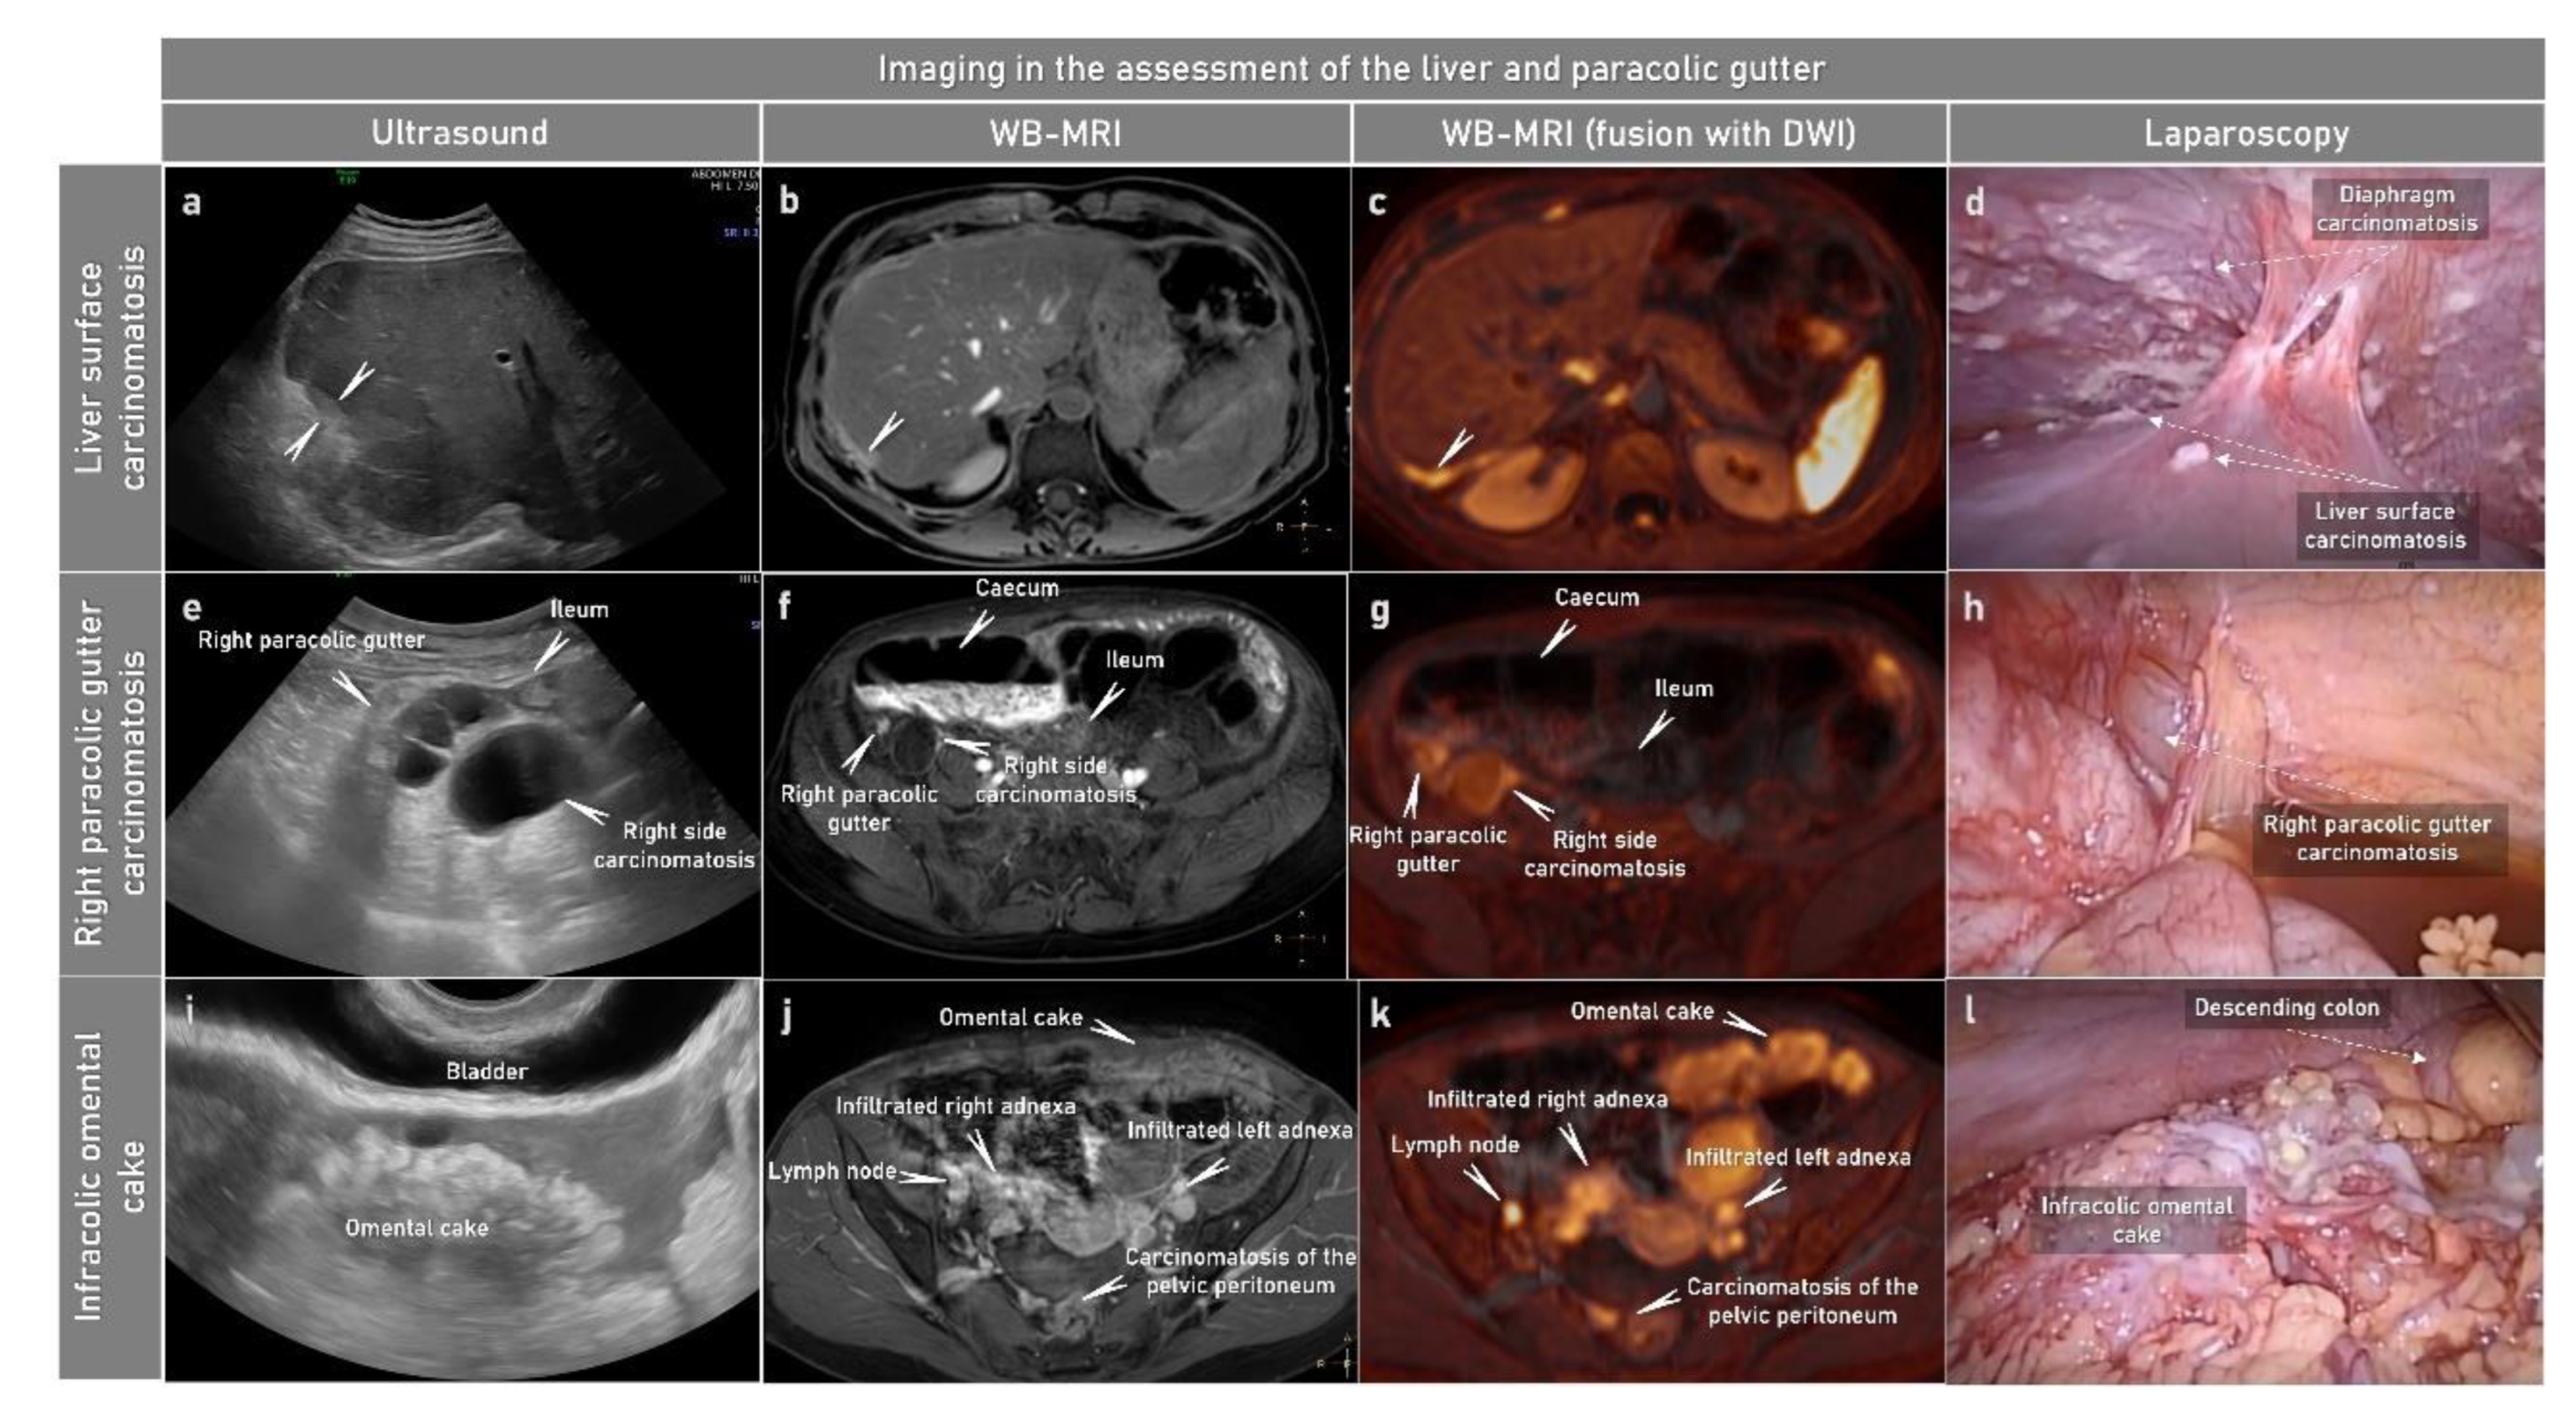

2.3.1. Ultrasound

2.3.3. Magnetic Resonance Imaging

2.3.4. Positron Emission Tomography